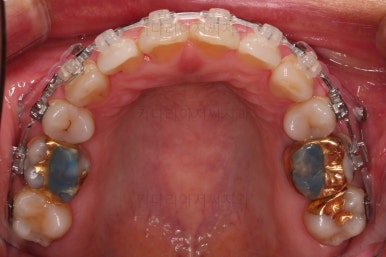

동래임플란트교정 초진 시 입안의 모습입니다.

비밀은 바로 화살표에 있습니다.

유치 잔존

말그대로 어릴 때 빠져야 할 유치가 남아있다는 뜻인데요.

앞니 사이에 뾰족하게 남아있다 보니 자리만 많이 차지하고 있는 모습이었고 다른 영구치를 더 삐뚤게 만들었어요.

딱히 영구치가 모자라진 않는데 유치가 잔존하는 굉장히 드물고 독특한 상황이었습니다.

당연히 유치는 뽑기로 했고요.

임플란트가 이미 있을 경우

임플란트는 교정이 되지 않습니다.

뼈에 단단히 붙어 있기 때문에 힘을 줘도 원하는 위치로 이동되지 않습니다.

이번 환자분의 경우 임플란트가 어금니 크기보다 작게 제작이 되어 있어서 추후에 교합을 맞추기도 곤란한 상황이었어요.

그래서 교정 후에 임플란트 뿌리 부분은 그대로 사용하고 머리 부분만 재제작 하기로 했습니다.